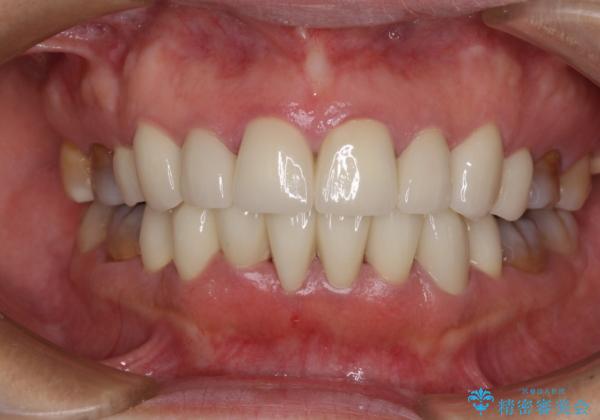

- 小さいころからの歯の変色と矯正治療の後戻りを気にして来院された患者様です。

気になる変色歯を仮歯に変え、その後歯列不正を矯正治療で改善し、最後にオールセラミッククラウンにて補綴治療することとしました。

数十年に及んだ歯の変色が改善されたため、大変満足していただきました。